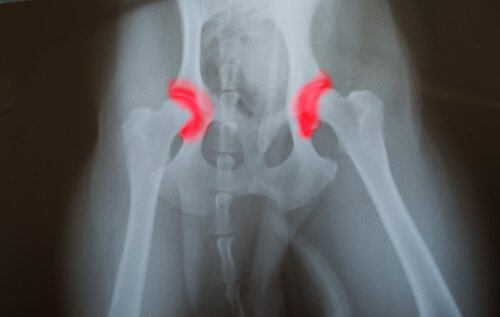

Hip or elbow dysplasia is a hereditary disease that passes from generation to generation. It is caused by the bones that form a joint — either it being the hip or the elbow — that are not placed or aligned correctly. This causes them to rub against each other and make improper movements. This causes an accelerated wear down which causes other problems that lead to the joints malfunctioning. The problem with this disease is that it is silent.